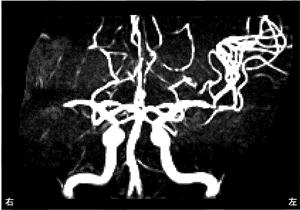

9

理学療法士実地問題 -

第45回 午前

重要度:標準

60歳の男性。来院時のMRAを示す。このMRAで病的所見を呈するのはどれか。

1

内頸動脈

2

前大脳動脈

3

前交通動脈

4

中大脳動脈

5

脳底動脈